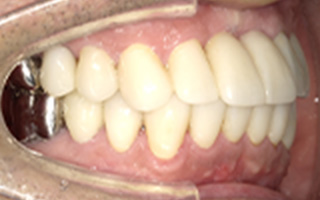

Before

After

| 68歳 男性 | 紹介 |

|---|---|

| 主訴 | れ歯が合わない 食べにくい 人生を豊かにしたい |

| 処置内容 |

上顎4本で12歯(オールオン4)、下顎4本5歯 上下抜歯即時埋入、即時荷重(手術当日にインプラントの上に仮歯装着) |

| 治療費用 | 上顎: 約220万(税込) 下顎: 約180万円(税込) |

| 治療期間 | 上顎: 9ヶ月 下顎: 6ヶ月 |

| リスク |

術後の腫れ、痛み(ピークは3日後、1週間で軽減) 上部構造物、仮歯の破折、人工歯根脱落リスクがあります |